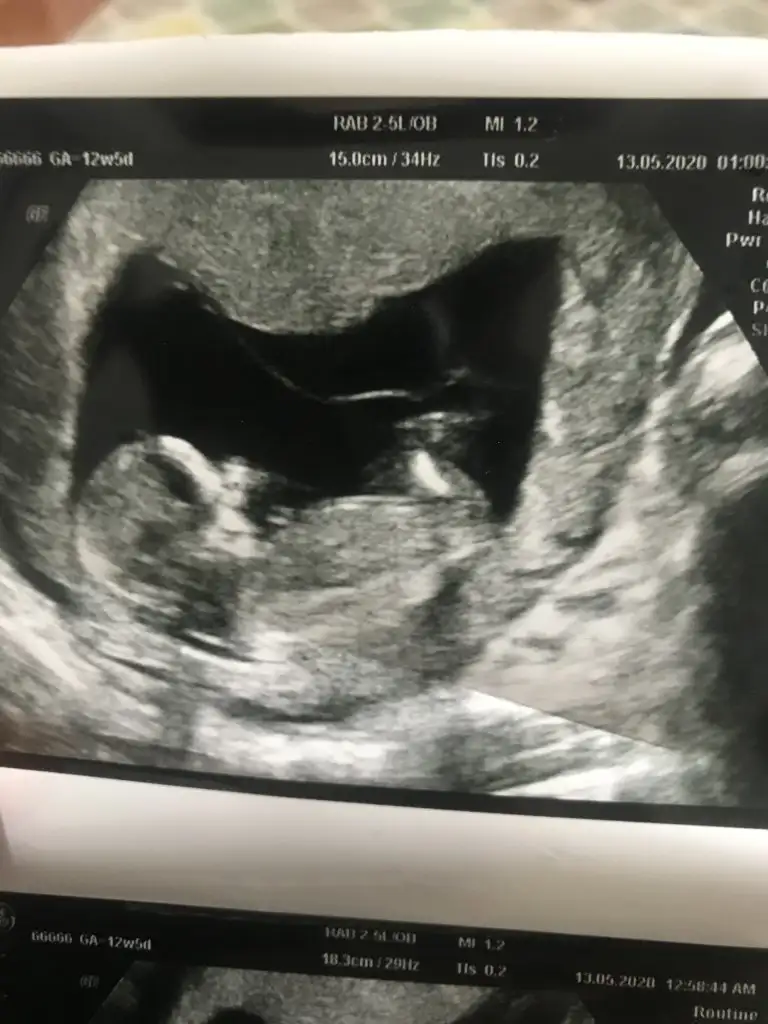

18. Haftadayım doktorum 15 haftalıkken %70 kız dedi çok uzun baktı görebilmek için ama şimdi kesin erkek dedi bir bakışta. Yanılma payı olurmu ki hislerim kızdan yana

11.hafta erkek dendi 13. Hafta kız dendi bu durumu yaşayanlar tekrar değişirmi